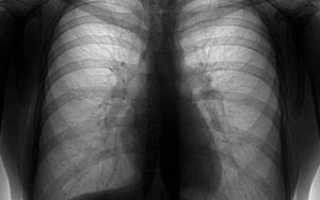

Флюорография лёгких фото

Пневмония – воспаление легких, которое может возникать в любом возрасте, но чаще у детей. Она разделяется по этиологии (вызвавшим ее возбудителям), степени тяжести, локализации воспаления (очаговая, крупозная, сегментарная, прикорневая и пр.). Фото снимков при пневмонии можно увидеть ниже.

Определить пневмонию можно с помощью данных аускультации и клиники; анализа крови (картина лейкоцитоза), инструментального исследования — флюорографии (ФЛГ) или рентгена легких – снимок легких при пневмонии.

На снимке легких при пневмонии получается, что негатив окрашивает самые плотные части в белый цвет, и кости в т.ч., пустые части – делает черными, органы – дают серые цвета разных оттенков.

Пневмония или воспаление хорошо визуализируется на рентгене и выглядит как инфильтративная тень на фоне усиления лёгочного рисунка, вокруг очага часто бывают просветления — локальная компенсаторная эмфизема.